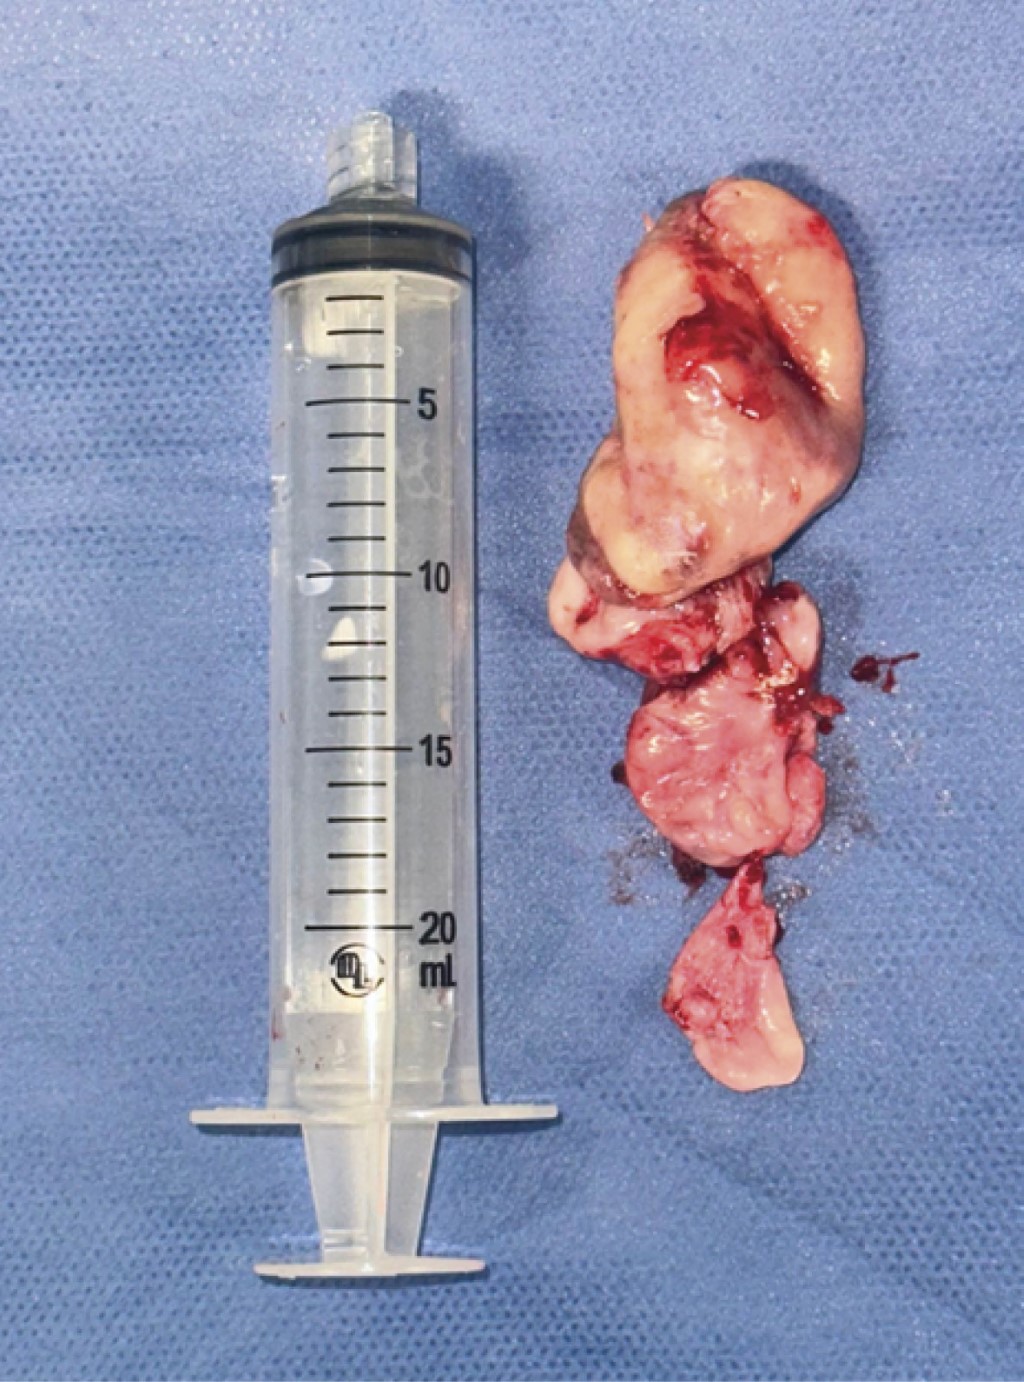

La disección del tumor se realizó de manera centrípeta, dirigiéndolo hacia cavidad oral en la cual se termina disecando y extrayendo el tumor por medio de la cavidad oral al exponerlo a la orofaringe. El tumor es enviado a estudio histopatológico (Figuras 8 y 9).

Figura 8

Figura 9